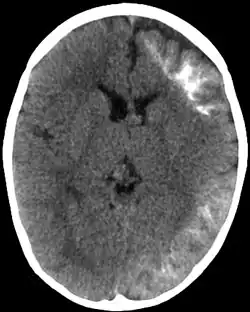

| CT scan of Sturge-Weber syndrome | |

Sturge–Weber is an embryonal developmental anomaly resulting from errors in mesodermal and ectodermal development. Unlike other neurocutaneous disorders (phakomatoses), Sturge–Weber occurs sporadically (i.e., does not have a hereditary cause). It is caused by a mosaic, somatic activating mutation occurring in the GNAQ gene.[2] Imaging findings may include tram track calcifications on CT, pial angiomatosis, and hemicerebral atrophy.[3]

CT and MRI are most often used to identify intracranial abnormalities. When a child is born with a facial cutaneous vascular malformation covering a portion of the upper or the lower eyelids, imaging should be performed to screen for intracranial leptomeningeal angiomatosis. The haemangioma present on the surface of the brain is in the vast majority of cases on the same side as the birth mark and gradually results in calcification of the underlying brain and atrophy of the affected region.[5]